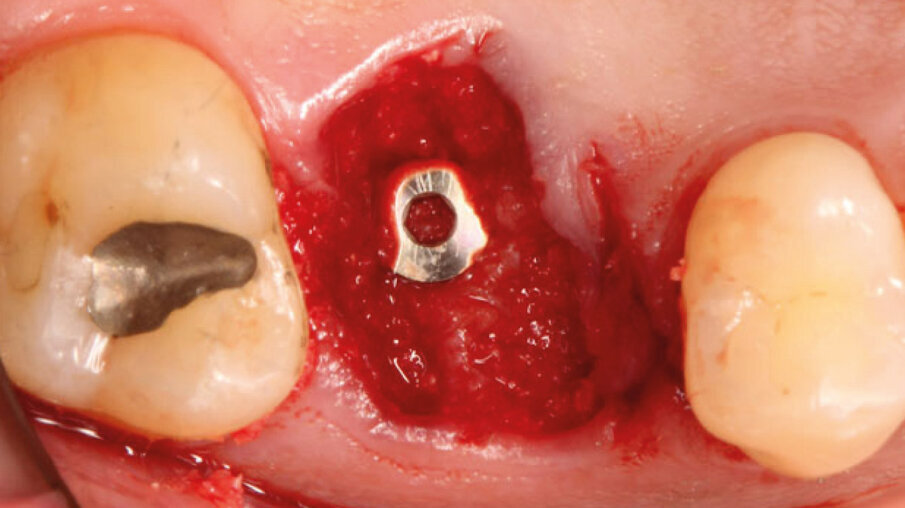

Dopo l’esecuzione dell’anestesia locale, il dente è stato rimosso e l’alveolo pulito dai residui del legamento parodontale. È stato inserito l’impianto (Zimmer TSV, Zimmer, Parsippany) 4.1 x 11,5 TSVM posizionato seguendo il protocollo consigliato dal produttore (Fig. 3). L’impianto è stato inserito a livello della cresta alveolare. È stato avvitato lo scan-abutment (Zfx Intrascan Matchholder, Zfx,). È stata rilevata un’impronta ottica intra-operatoria dell’emiarcata in cui è stato posizionato l’impianto con lo scan abutment (Fig. 3). Il gap tra l’osso vestibolare e l’impianto è stato riempito con Bio-Oss (Geistlich Pharma) (Fig. 4). Al termine della chirurgia è stato progettato e fresato il provvisorio, che è stato applicato appena pronto, dopo aver inserito la matrice in collagene volumetricamente stabile Fibro-Gide (Geistlich Pharma) precedentemente imbibita con il gel a base di polinucleotidi e acido ialuronico Regenfast (Officine Bio-Farmaceutiche Mastelli), al di sotto della vite stessa (Figg. 5, 6). Data l’accuratezza della vite non sono state necessarie suture. Al termine della procedura è stata eseguita una radiografia di controllo (Fig. 7).

Fig. 4 - Inserimento implantare con zappatura del gap con Bio-Oss.